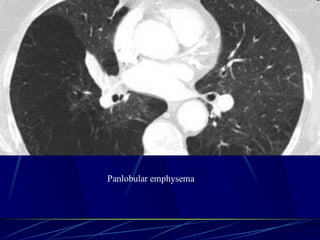

Panlobular emphysema

Affects the whole secondary lobule

Lower lobe predominance

In alpha-1-antitrypsin deficiency, but

also seen in smokers with advanced

emphysema

Affects the entire secondary pulmonary

lobule and is more pronounced in the lower

zones

Complete destruction of the entire pulmonary

lobule.

Results in an overall decrease in lung

attenuation and a reduction in size of

pulmonary vessels

124